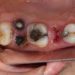

牙齒痺痛原因1. 深層齲齒(蛀牙)侵犯牙本質

這是最常見的牙齒麻痺原因之一!當細菌長期侵蝕牙齒,齲洞穿透牙釉質到達牙本質層,牙本質內部的小管直接連接牙髓神經,此時冷熱酸甜食物都會刺激神經,引發短暫的麻痛感,有時還伴隨「牙齒麻麻痛痛的」異物感。香港牙科醫學會2026年門診統計顯示,25-45歲人群中,63%的牙齒痺痛與深層齲齒相關,很多人因為初期疼痛不明顯而延誤治療,導致齲洞進一步加深。